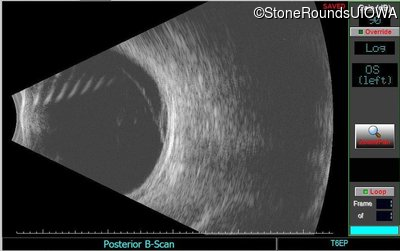

B-Scan Ultrasonography - Left - Light Perception

Exemplar

B-Scan Ultrasonography - Left - 20/600 sc